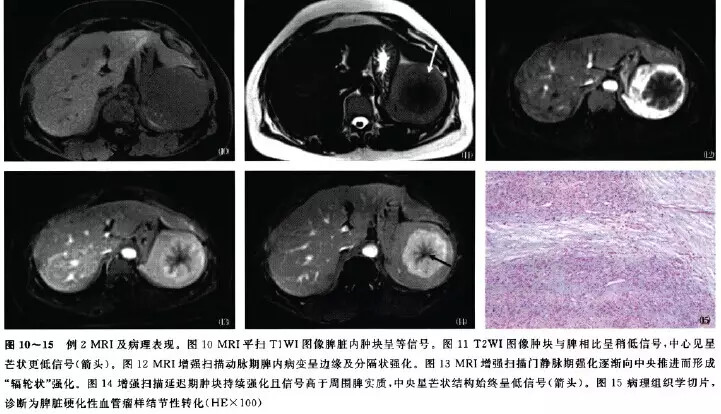

MRI见肿块状呈浅分叶,边界清楚。T1WI呈等信号,T2WI与脾相比呈稍低信号,中心见星芒状低信号。动脉期呈边缘及分隔状强化,门静脉期强化逐渐向中央推进而形成“辐轮状”强化,延迟期持续强化且信号高于周围脾实质,中央星芒状结构始终呈低信号(图10~15)。

术后病理:脾硬化性血管瘤样结节性转化。免疫组织化学检查:CD31( )、CD34( )、CD68( )、SMA(-)、DES(-)、F8( )、S-100( )、ALK(-)。